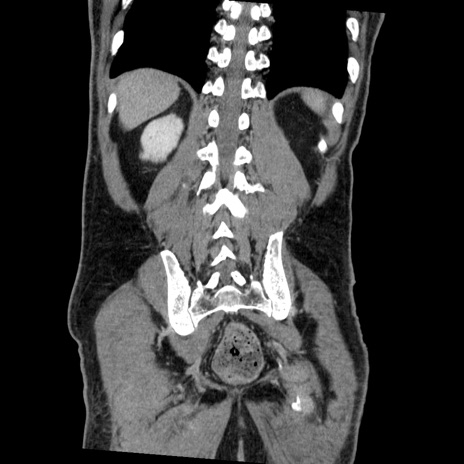

症例22(冠状断像)

【症例】50歳代男性

【主訴】腹痛

【現病歴】AVMからの被殻出血のため回復期リハ病棟入院中。 本日午後3時頃急に下腹部痛が出現した。

【既往歴】AVM、被殻出血、虫垂炎、高血圧

【身体所見】意識晴明、左半身不全麻痺、会話の理解は良好、36.5°C、腹部:膨隆、全体に板状硬、下腹部正中に圧痛点あり、反跳痛-、筋性防御不明、右下腹部にope scar

【データ】WBC 9400、CRP 0.06

横断像